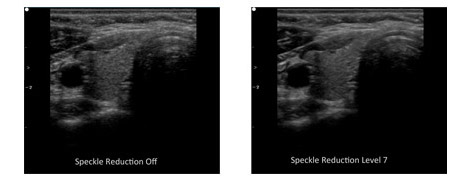

Speckle Reduction Technology

Speckle reduction imaging uses real-time image processing to improve visualization of anatomy and pathology by reducing the speckle noise. Edan's speckle noise reduction imaging technology uses an advanced multi-scale anisotropic filtering algorithm. This imaging technology is excellent at separating the noise regions from the diagnostic image allowing complex filtering to be performed differently on noise versus true anatomic information thus producing an enhanced image